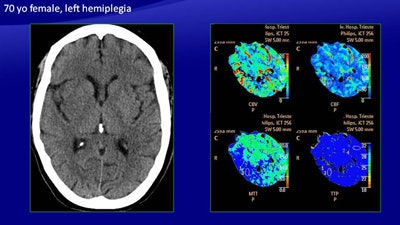

In the study, 26 patients with ischemic stroke underwent perfusion imaging in addition to noncontrast CT. Perfusion and core maps were automatically generated, along with separate evaluation of cerebral blood flow (CBF), cerebral blood volume (CBV), and mean transit time (MTT). The results showed that the manually generated maps were at least 10% more accurate than automatically derived maps, the researchers from Trieste, Italy, found.

"Analysis of the manually generated maps had greater sensitivity in comparison with the maps generated by the software, in particular in the infratentorial area and in the basal ganglia area [where] it tends to underestimate the extent of perfusion" said Dr. Maja Ukmar from the department of radiology at the University of Trieste.

The study aimed to compare the accuracy of manually generated perfusion maps (CBF, CBV, MTT) with maps generated automatically by commercially available software (Brain Perfusion, Philips Healthcare) for the definition of infarct core and penumbra in acute ischemic stroke patients less than five hours after symptom onset.

All imaging was performed with a 256-detector-row scanner (Brilliance iCT, Philips), beginning with noncontrast CT at admission and then perfusion CT after injection of 75 mL of contrast media (followed by 40 mL of saline at 4 mL/sec). Perfusion images were acquired every four seconds for a total scan duration of 60 seconds at 80 kV and 150 mAs to 200 mAs.

Manual image processing was used to generate perfusion maps, followed by the software maps, "in which the green area meets the criteria for penumbra, and the red area meets the criteria for the infarct core," Ukmar said.